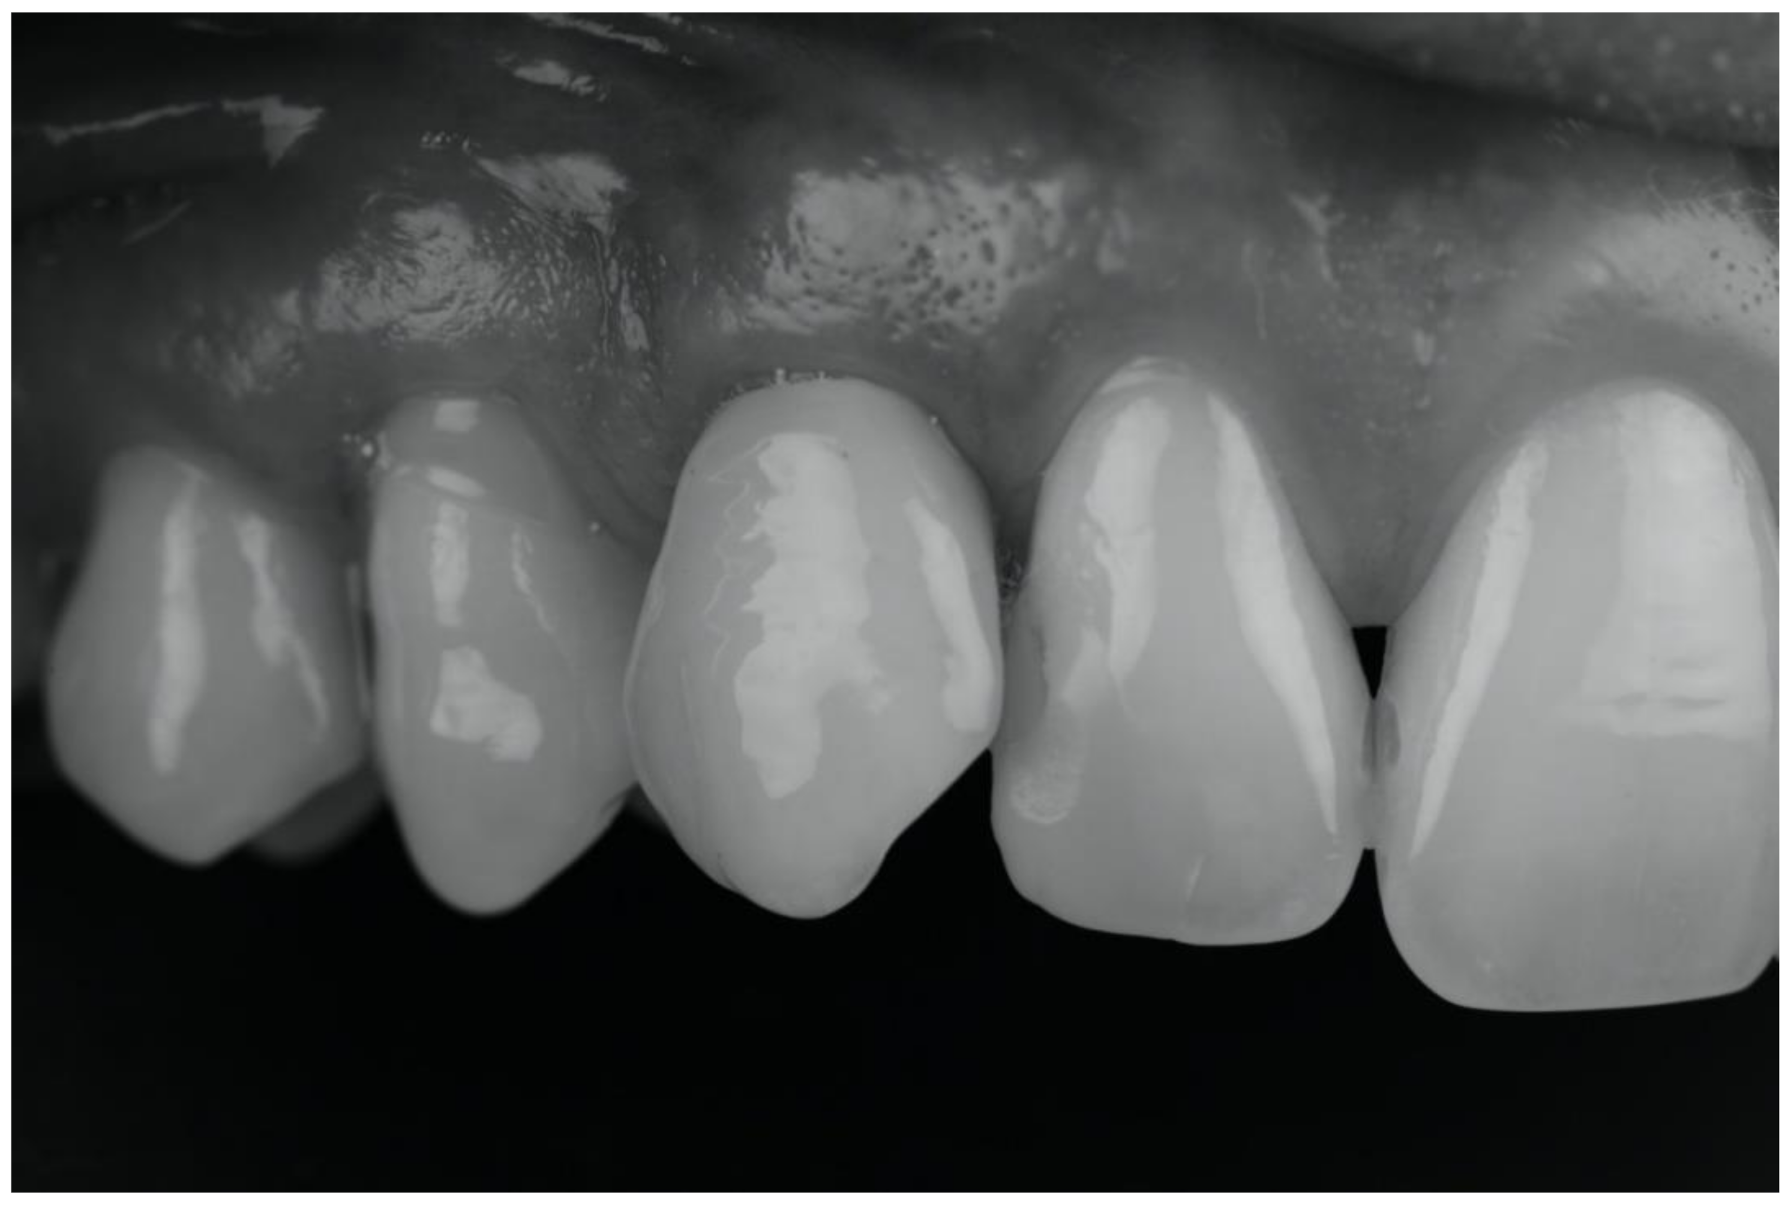

| (a) Surgical removal of the deciduous tooth and orthodontic extrusion, and taking in occlusion of the permanent canine |

| (b) Conservative treatment of the deciduous tooth living in situ with the impacted canine |

| (c) Removal of the deciduous tooth and involvement of the adjacent natural elements for a fixed conventional or adhesive bridge living in situ with the impacted canine |

| (d) Removal of the deciduous tooth and replacement with implant-borne-prosthesis living in situ with the impacted canine, accepting the compromise of involving the impacted tooth in the implant seating procedure |

| (e) Surgical removal of the impacted canine and, in a second stage, removal of the deciduous tooth and replacement with implant-borne-prosthesis |